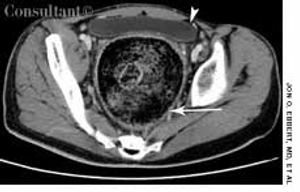

A 31-year-old man with a history of traumatic brain injury was hospitalized because of failure to thrive, constipation, and intermittent diarrhea with soiling.